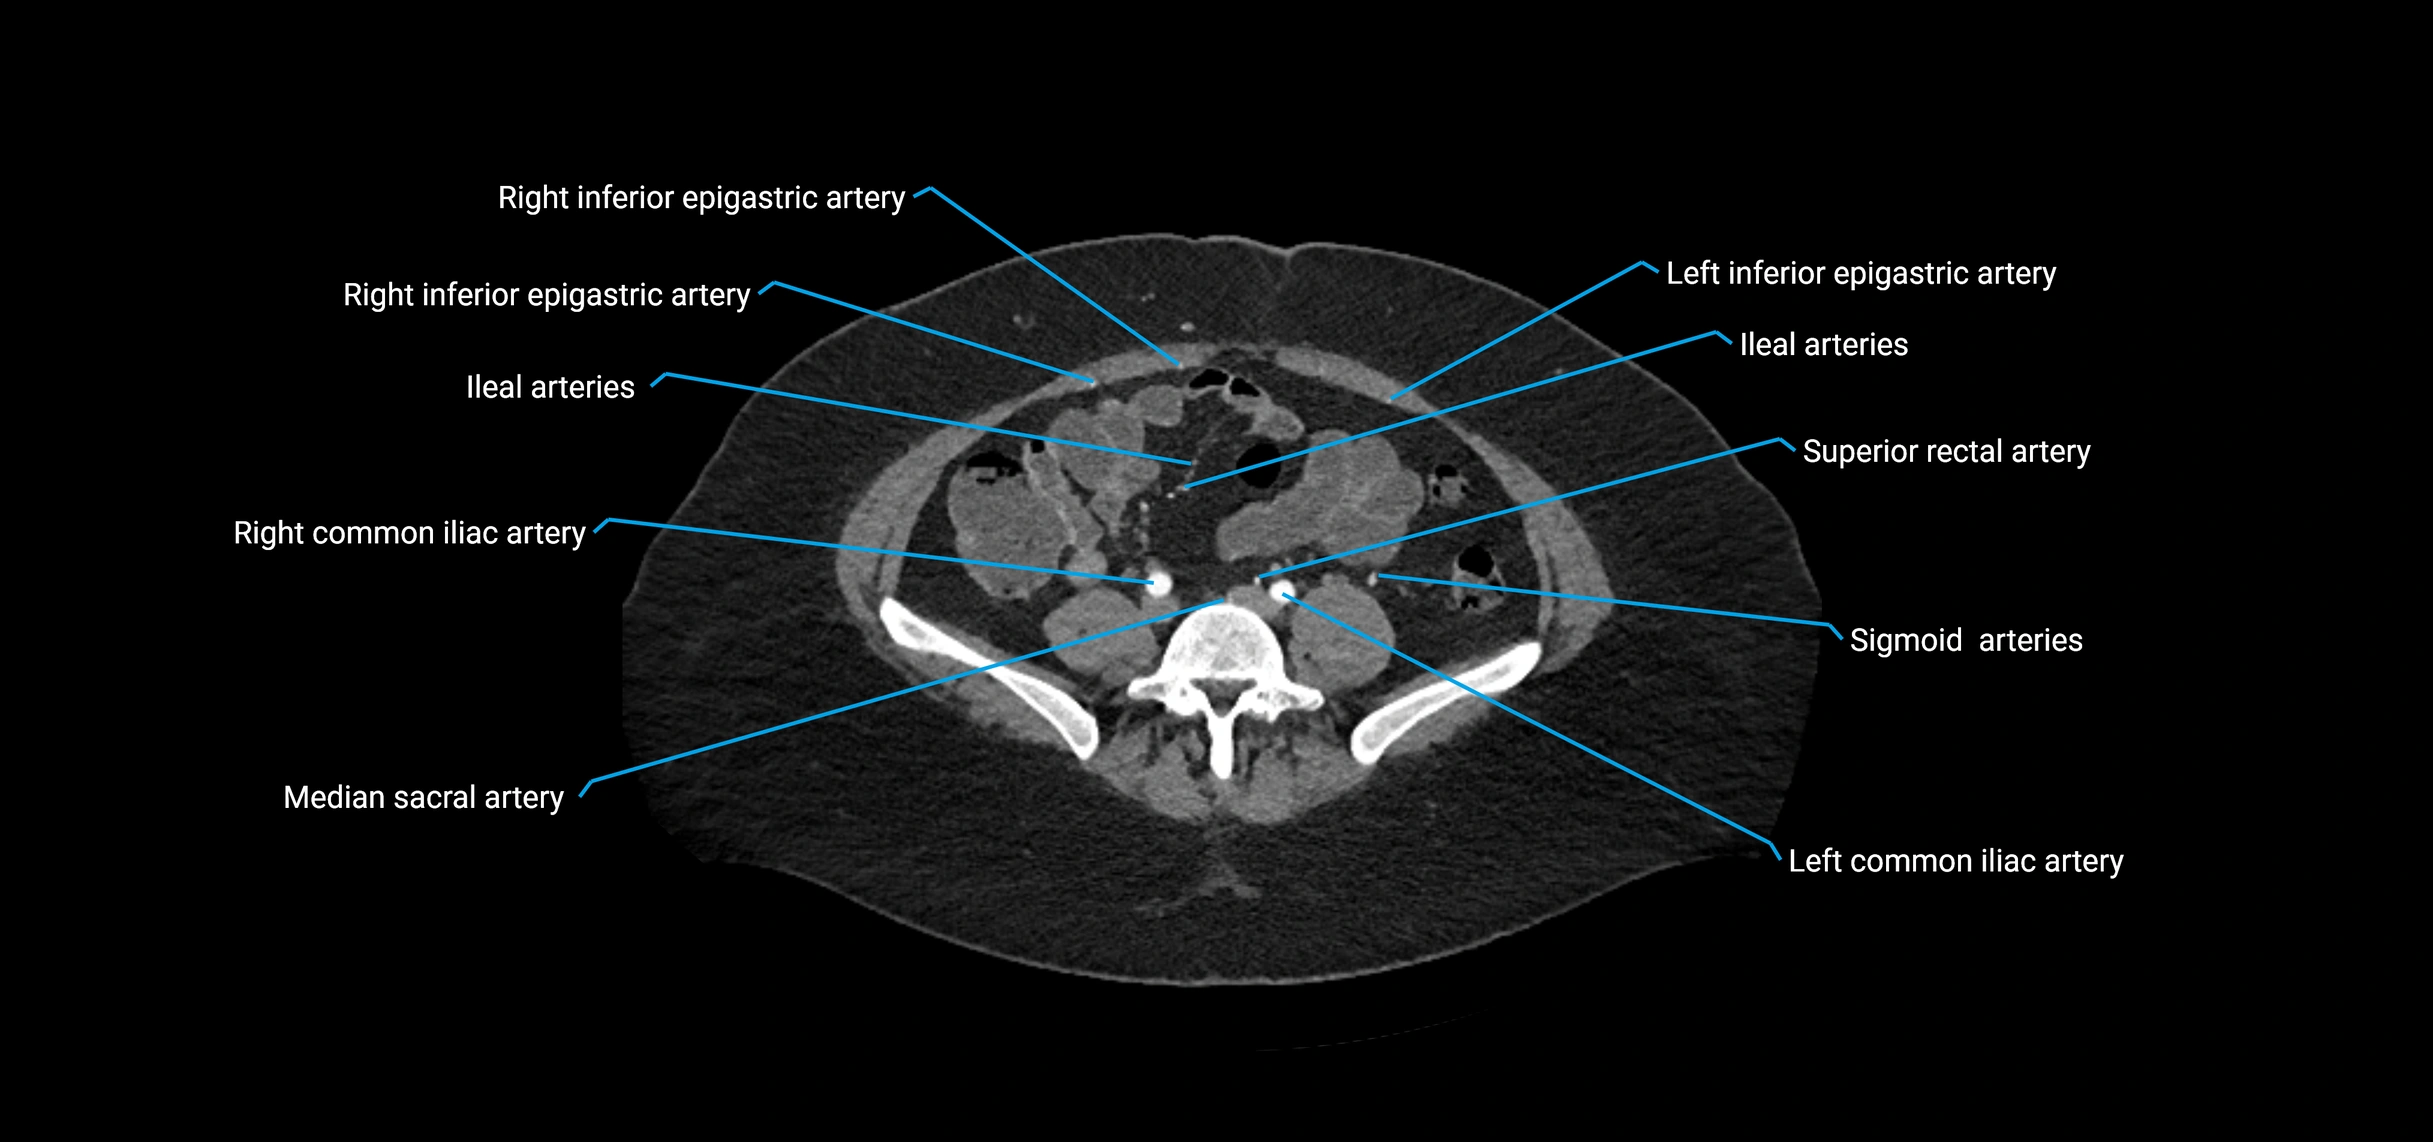

CT images

image

Contrast-enhanced CT (CTA):

• Gold standard for abdominal aortic imaging

• Provides excellent detail of lumen, wall, aneurysm, thrombus, and branch vessels

• Multiplanar and 3D reconstructions help in aneurysm measurement, stent graft planning, and dissection evaluation